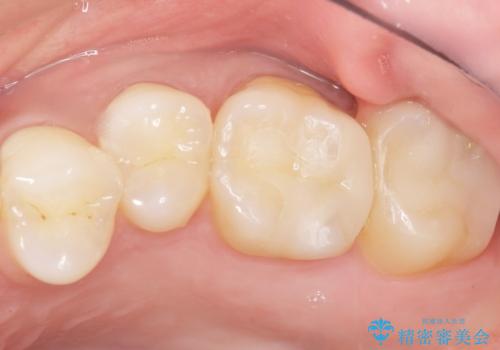

不適合なレジンを除去し、セラミックインレーによる治療を行いました。(右上76左上67右下7の計5本)

気にされていたフロスをした時のにおいがなくなり、喜んで頂けました。

治療終了後半年のメンテナンス時には「咬み合わせもばっちりです!」とおっしゃって下さいました。

インレーの種類:セラミックインレー e-max press